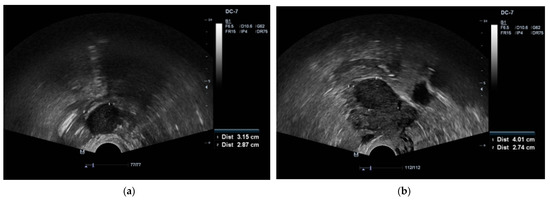

A 65-year-old Caucasian female (parity 2, abortions 1, and miscarriages 0) presented to an endocrinologist due to excessive body hairiness and alopecia. Over the past year she experienced these symptoms, which caused the patient significant psychological distress. The patient experienced menopause at age 55 years. She had a history of hysteroscopic polypectomy and other concomitant diseases, including primary hypertension, neurosensorial hearing loss, non-toxic multinodular goiter, obesity, detected multiple cystic lesions in the pancreas, characteristic of intraductal papillary mucinous neoplasm (IPMN), as well as bilateral parapelvic renal cysts. A Pap smear was performed several years ago, but the patient did not know the results. Laboratory testing showed increased levels of serum testosterone and dehydroepiandrosterone sulfate: total testosterone 25.96 nmol/L (normal range, 0.43–1.24), dehydroepiandrosterone sulfate (DHEA-S) 6.25 µmol/L (normal range, 0.8–4.9). Transvaginal ultrasound revealed the presence of two tumors in both ovaries, with the right measuring 3.1 × 2.8 cm and the left measuring 4.0 × 2.7 cm (Figure 1a,b).

Figure 1. (a) Transvaginal ultrasound of a 3.1 × 2.8 cm lesion in the right ovary. (b) Transvaginal ultrasound of a 4.0 × 2.7 cm lesion in the left ovary.